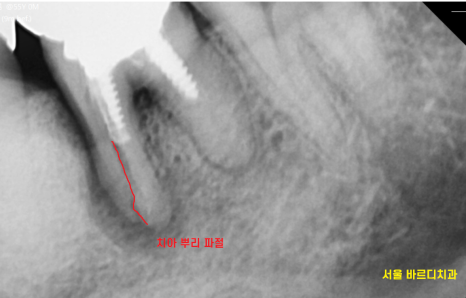

딱봐도 이상해보이는 치아를

정밀하게 검사해보니

치아뿌리 파절, 부러짐이 확인되었습니다.

그 상태에서 자꾸 씹다보니

뿌리 주변 뼈가 녹아서

까맣게 보이네요~